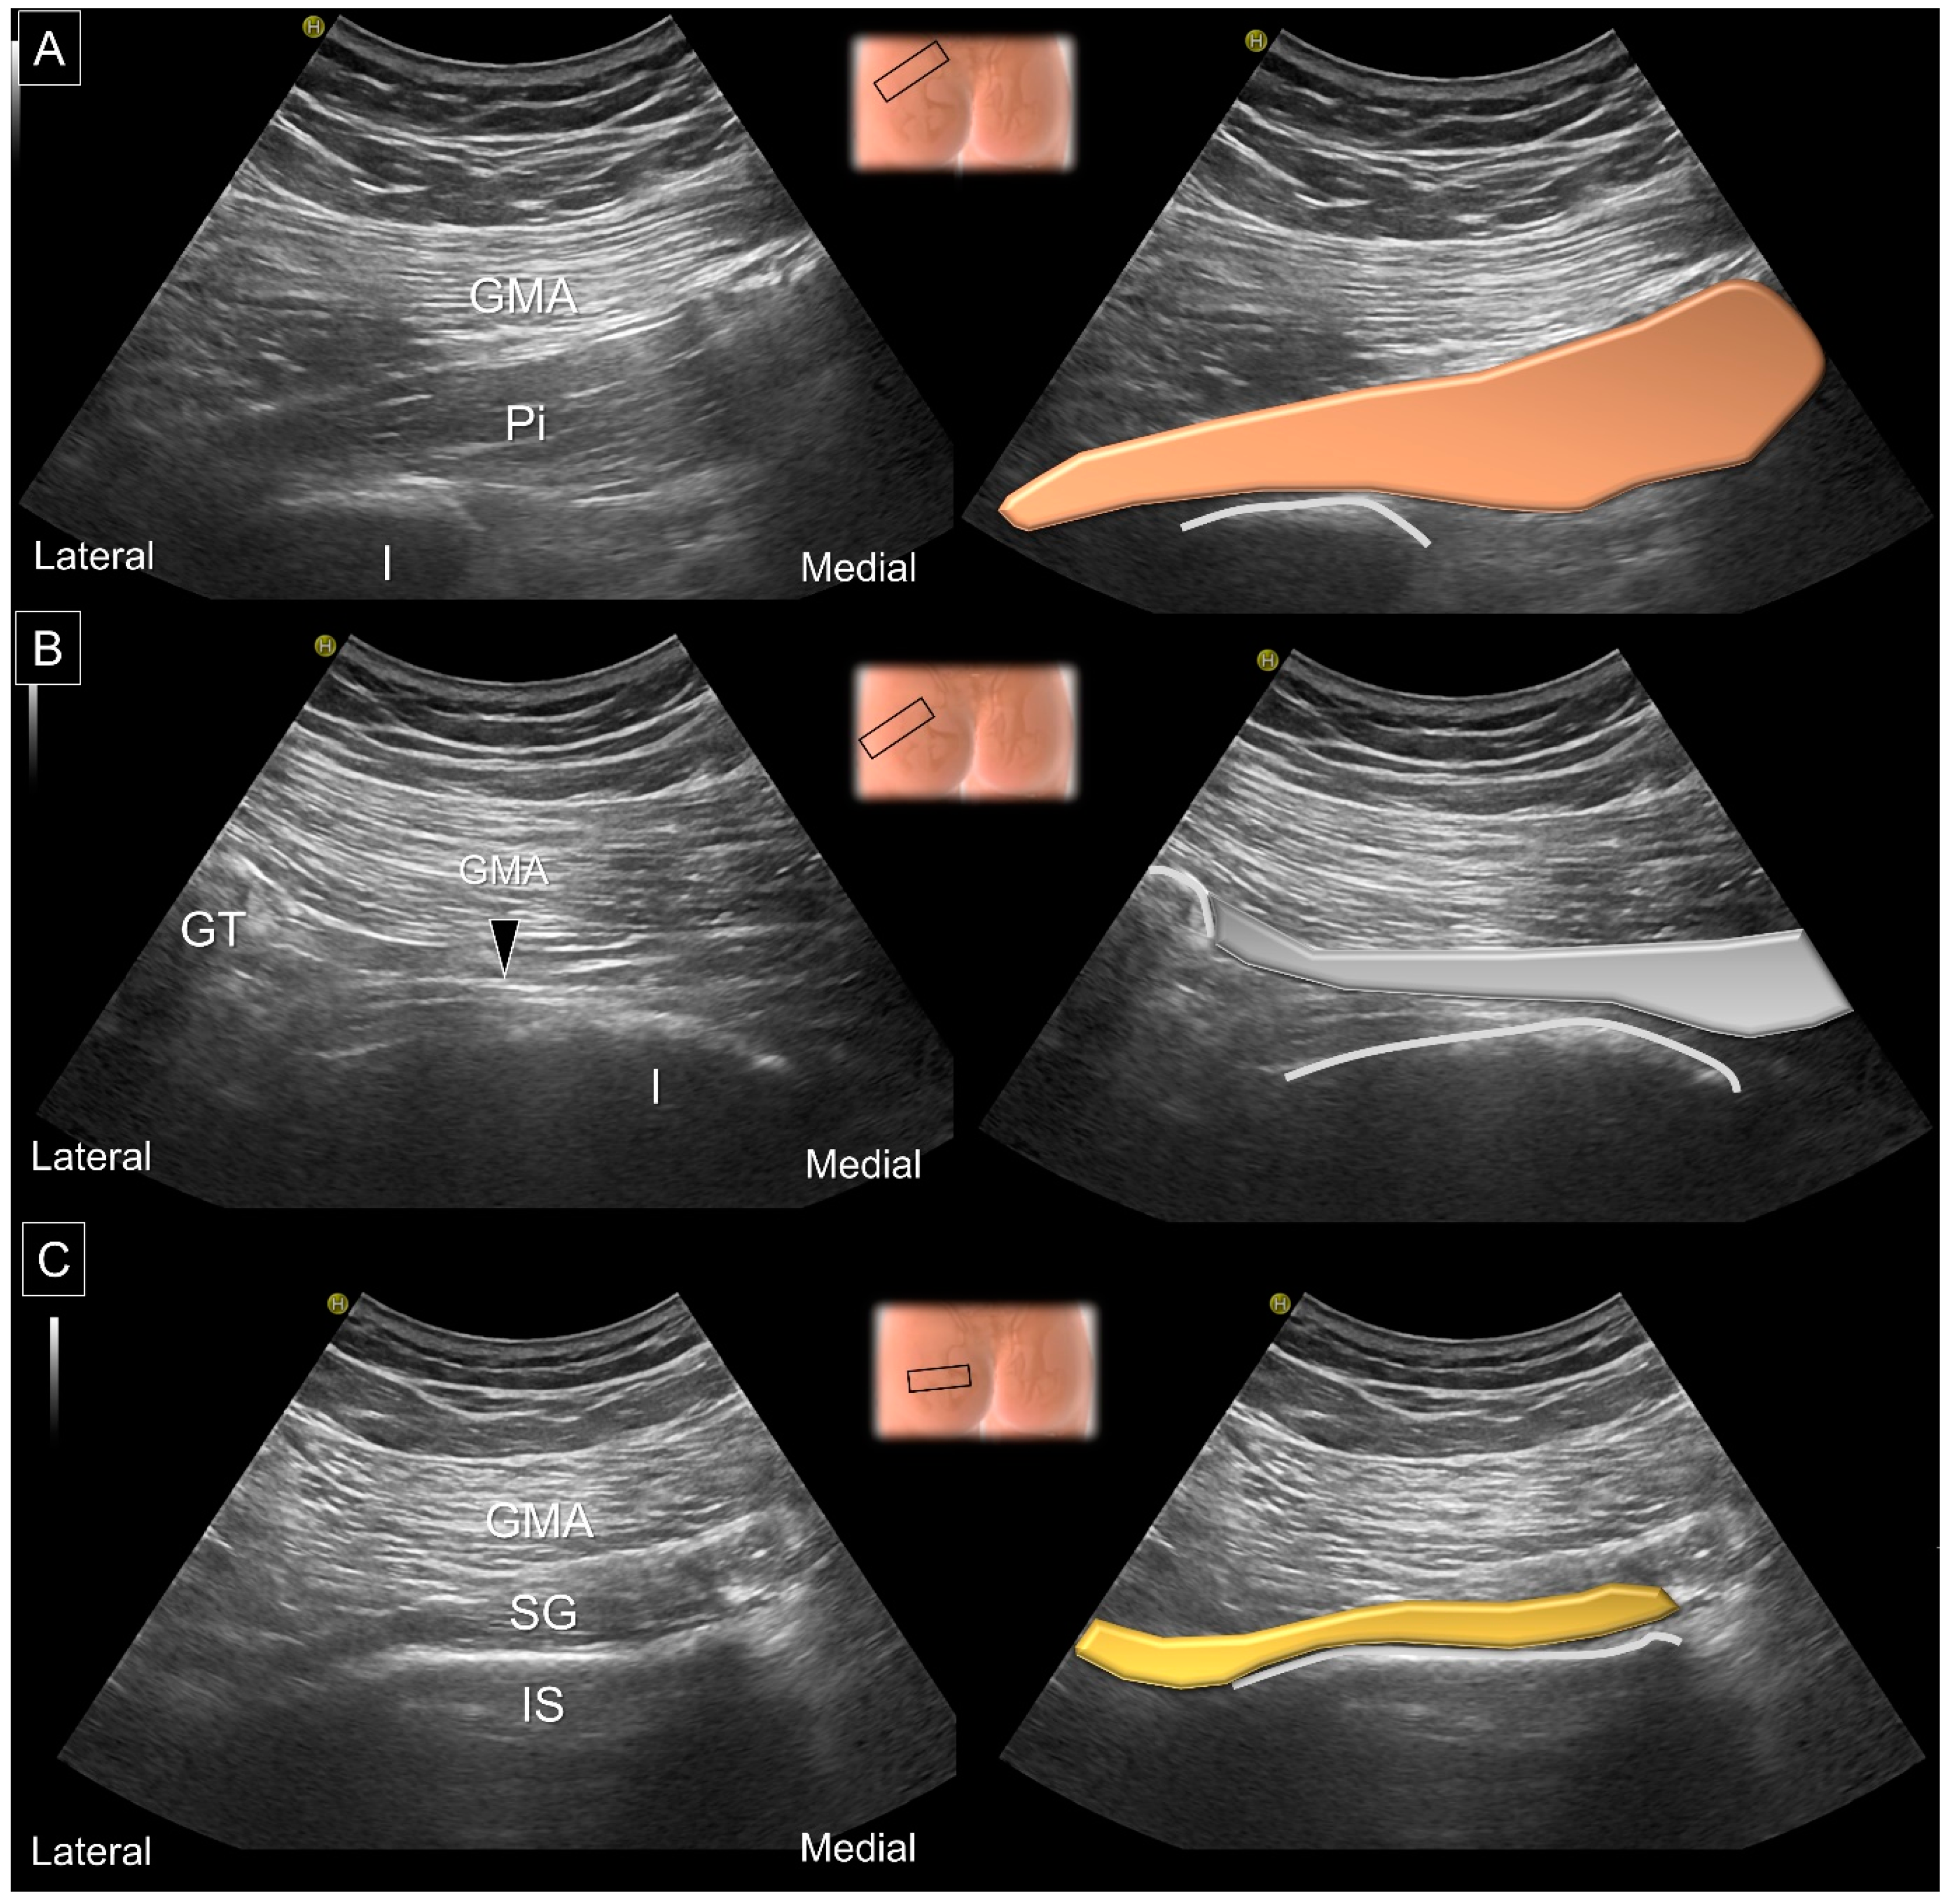

8. Dynamic Ultrasound Evaluation